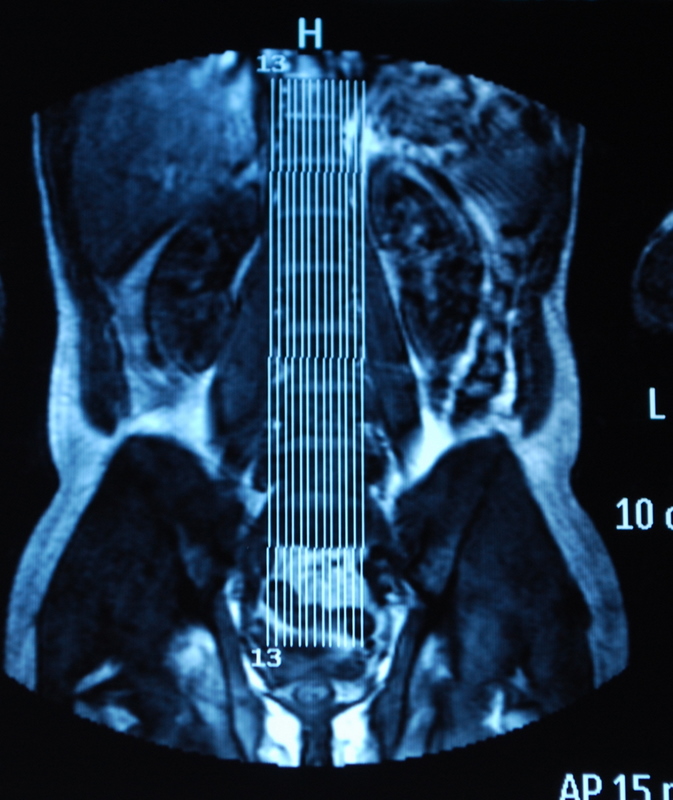

I’ve also come back with copies of my scans. Its very bizarre to sit there and look at slices through your own body. Forget losing weight so you look good in your holiday or wedding photos, try an MRI. There is no turning your best side to the camera or wearing stripes the right way round to hide/accentuate your curves. It shows all your fat, in lovely cross sectional detail. Cath also pointed out that she can see poo in some of the films! Nice…..

Apparently, I’ve also got a dehydrated disc on the next one up (L3/4) which might cause me issues in later life if I’m not careful with impacts, too.